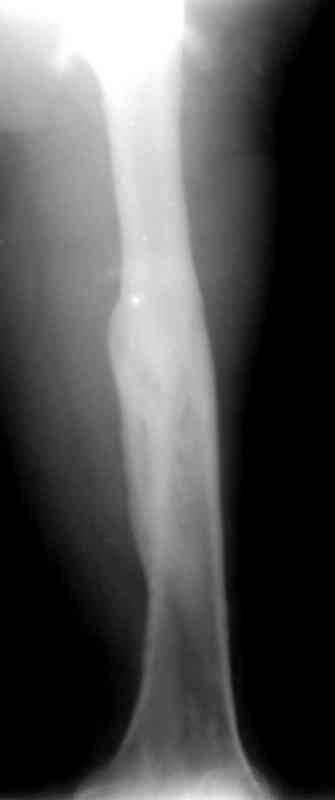

по его наружной поверхности послеоперационный рубец - рана зажила первичным натяжением. При измерении длины бедер обнаружено укорочение левого бедра на 4,5 см. На рентгенограммах этого бедра: ось конечности правильная, отмечается захождение основных костных фрагментов по длине, проксимальный конец штифта выступает слишком медиально и высоко относительно большого вертела, периостальная мозоль незначительна.22.12 - через 6 месяцев после операции, произведенной в ЦРБ, нами по поводу замедленно консолидирующего перелома левой бедренной кости с ее абсолютным укорочением под наркозом произведена операция: удаление штифта, закрытый блокирующий интрамедуллярный остеосинтез перелома левого бедра штифтом без рассверливания (UFN) длиной 40 см, диаметром 10 мм с блокированием только проксимальных отверстий (динамический остеосинтез). Наложен аппарат Илизарова на 4 полукольцах с целью удлинения укороченного бедра. Послеоперационное течение без особенностей. Ежедневно осуществляли дистракцию отломков на 1 мм. Через 3 недели после операции больной выпи-сан на амбулаторное лечение с продолжением дистракции отломков. В течение 1,5

месяцев дистракции укорочение левого бедра удалось полностью устранить. 22.02.00, т.е. через 2 месяца после повторного остеосинтеза, больному произведено дистальное блокирование штифта двумя винтами и демонтирован аппарат Илизарова. В течение 2 недель после операции больной ходил с помощью костылей, потом 2 недели с тростью. Опороспособность и функция оперированной конечности полностью восстановились через 4 недели после операции.

Фиксаторы удалены через 12 месяцев после операции, выполненной по поводу замедленной консолидации перелома бедра с его укорочением.

Спасибо! Истинно мастерская работа. Представляю как счастлив пациент исходом этой истории.

На финальных снимках видно - сращение прям таки железное. Если Вы не устали отвечать, осмелюсь задать еще вопрос - что-то принимал пациент в целях ускорения сроста (кальций, режим питания). Интересны также вопросы восстановления функций конечности - в какой период были рекомендованы группы упражнений для восстановления основных групп мышц?